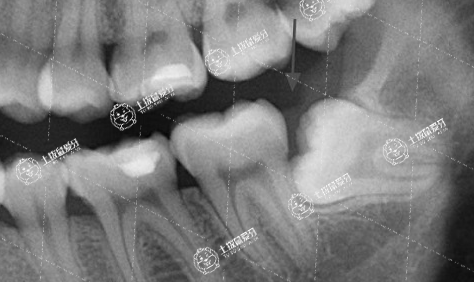

其次,在矯正的過程中,發(fā)現(xiàn)智齒的存在對于牙齒矯正有阻礙,譬如智齒屬于剛剛開始萌發(fā)的狀態(tài),并且可以明顯看出位置不當(dāng),對于以后的牙齒矯正會有影響的,或者占據(jù)了正常牙齒部分位置,使得牙齒矯正無法正常進(jìn)行的,即便矯正好牙齒,沒有拔除的智齒也容易造成牙齒移位,導(dǎo)致效果反彈,最好要拔除智齒。

1、智齒不能正常萌出

這種智齒就像一顆定時(shí)炸彈,即使不進(jìn)行牙齒矯正也需要及時(shí)的拔除。

2、牙列擁擠

正畸醫(yī)生會優(yōu)先考慮拔除智齒或多生牙來留出足夠的空間進(jìn)行牙齒矯正。